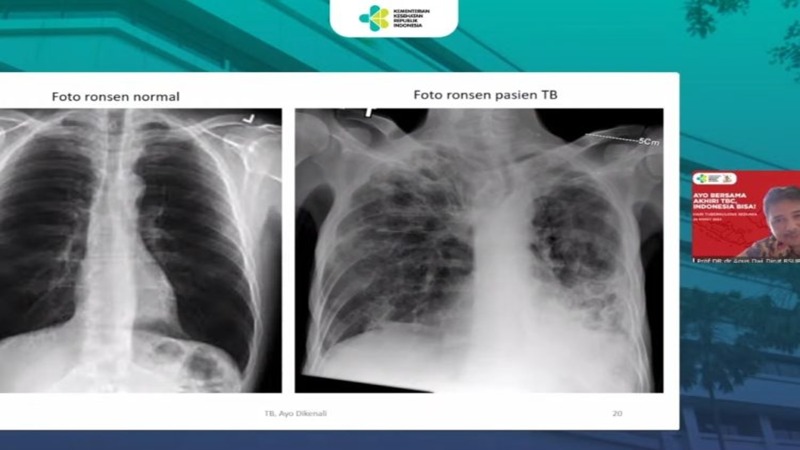

Perwakilan dari Perhimpunan Dokter Paru Indonesia Prof dr. Dwi Sutanto mengatakan hampir semua organ tubuh manusia bisa terkena TBC, tetapi yang paling sering adalah paru-paru.

Gejala seseorang terinfeksi TBC adalah batuk-batuk berdahak, batuk berdarah, sesak napas, lemas, nafsu makan menurun, berat badan menurun, berkeringat malam hari, dan demam meriang.